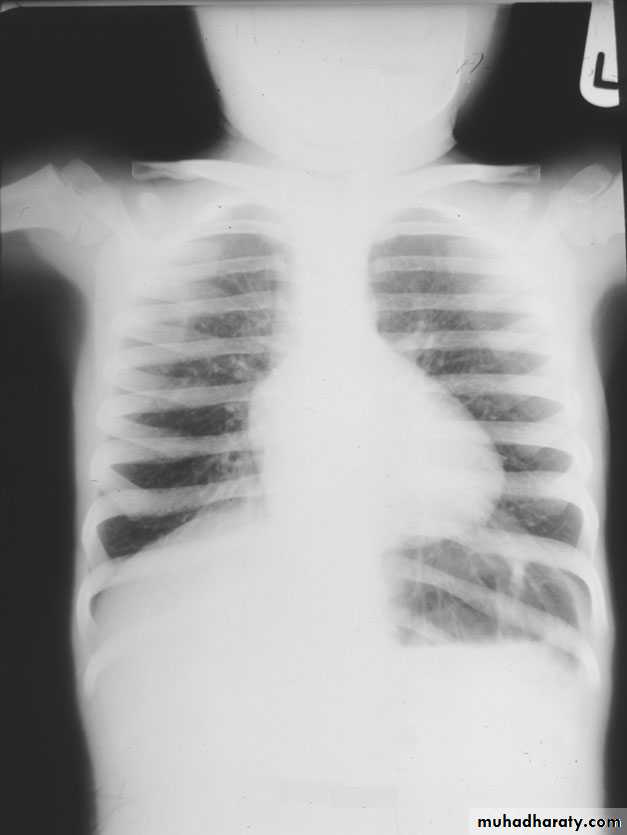

Miliary tb